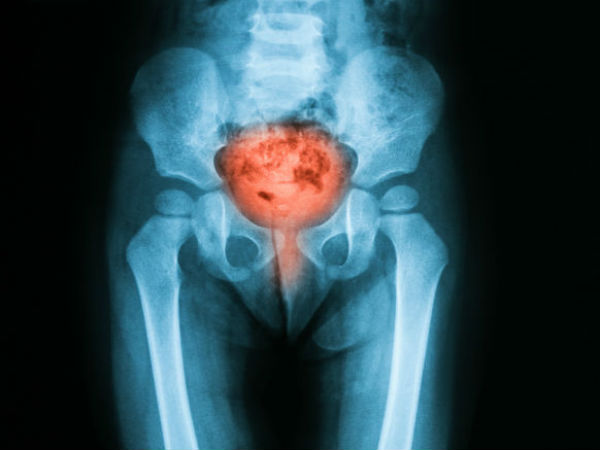

உடனடியாக மருத்துவரை அணுகிய ஜாராவின் வயிற்றைப் பார்த்து கர்ப்பப்பையில் கட்டியிருக்கும் என்றார் மருத்துவர். இருந்து அல்ட்ராசவுண்ட் ஸ்கேன் எடுத்து பார்தபோது சரியாக கண்டுபிடிக்கமுடியவில்லை.

அதன் பின்னர் ரேடியோகிராபர் ஒருவரிடம் சென்று காண்பித்தபோது அவர் எம்.ஆர்.ஐ., ஸ்கேன் எடுத்து பார்த்துள்ளார். அதில் தான் உண்மை வெளிப்பட்டிருக்கிறது.

மருத்துவ அதிசயம் :

இத்தனை ஆண்டுகாலமாக ஜாராவின் வயிற்றுக்குள் இருந்த குழந்தை அது. சுமார் 46 ஆண்டுகளாக வயிற்றுக்குள்ளேயே இருந்திருக்கிறது.

கர்ப்பமாக இருக்கும் போது கரு கர்ப்பப்பையை விட்டு ஃபாலோபியன் டியூபிற்குள் வந்திருக்கும். அதனை சுகப்பிரசவம் நடப்பது மிகவும் சிரமமமானது. சிசேரியன் மூலமாகத்தான் குழந்தையை வெளியே எடுக்க முடியும்.

இது போன்ற சம்பவங்களில் கவனமாக இல்லாவிட்டால் தாயின் உயிருக்கே கூட ஆபத்து ஏற்படக்கூடும். ஆனால், ஜாரா இவ்வளவு ஆண்டுகள் உயிருடன் இருந்தது அதிசயம் என்கிறார்கள் மருத்துவர்கள்.

உள்ளேயே இறந்த அந்த குழந்தை நாளுக்கு நாள் கட்டியாக உணவாக எடுத்துக் கொள்ளும் கால்சியம் அதிகம் உறிஞ்சப்பட்டு, இறந்த அந்த குழந்தை கல்லாக மாறியுள்ளது. இப்படி மாறவில்லையெனில் ஜாராவிற்கு நோய்த்தொற்று ஏற்பட்டு மரணம் கூட நிகழ்ந்திருக்கும்.

அதீத வலியால் துடித்த ஜாராவிற்கு இறுதியாக அவருக்கு அறுவை சிகிச்சை மேற்கொள்ள முடிவு செய்யப்பட்டது. ஆனால் 75 வயதை நெருங்கிவிட்டாதல் இந்த அறுவைசிகிச்சை மேற்கொண்டால் மற்ற உறுப்புகளுக்கு ஏதேனும் பாதிப்பு உண்டாகுமா என்கிற அச்சமும் எழுந்தது.

எனினும் இதனை சவாலாக ஏற்றுக் கொண்ட மருத்துவர்கள் சுமார் 4 மணி நேரம் நடைப்பெற்ற அறுவை சிகிச்சையின் மூலம் அந்த கல் குழந்தையை அகற்றினர்.

தற்போது ஜாரா நலமுடன் உள்ளார்!